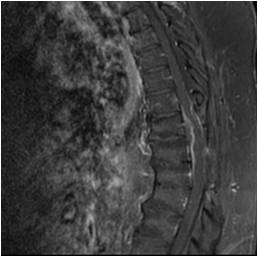

Idiopathic Hypertrophic Pachymeningitis

A chronic progressive diffuse inflammatory fibrosis of the dura mater. Diagnosis of exclusion since meningioma, lymphoma, sarcoid and TBc can present in a similar fashion. MRI findings of low signal intensity mass extending over several levels with linear or nodular peripheral enhancement (representing active inflammation) highly suggestive of the diagnosis. [ Article ]

chronic myelopathy with several decompressions

Courtesy Jay A Kaiser MD